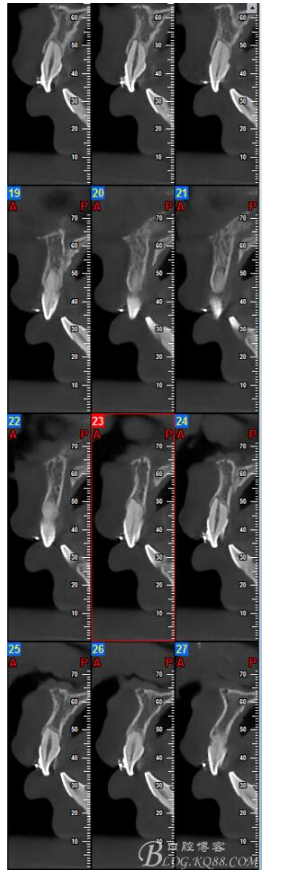

鐘佳溪:正畸治療不可忽視的副作用——牙根再吸收

對牙根再吸收的研究持續(xù)了一個(gè)多世紀(jì)。 一般被認(rèn)為是正畸治療的一個(gè)不可避免的副作用。當(dāng)正畸力中斷或減低到某個(gè)水平以下時(shí),牙周組織中的修補(bǔ)過程即開始,并隨著時(shí)間而加強(qiáng)。生物和機(jī)械因子影響正畸誘導(dǎo)的炎癥性牙根吸收的嚴(yán)重程度。臨床醫(yī)師能夠通過控制機(jī)械誘因來減小牙根吸收的副作用并啟動修復(fù)。

有15%的人在正畸治療前就已經(jīng)發(fā)生牙根吸收,這與激素失衡和飲食缺乏有關(guān)。正畸治療后12個(gè)月,牙根再吸收的發(fā)生率增加到73%,有25%的正畸治療患者根尖吸收超過2mm,約5%的人發(fā)生超過5mm的嚴(yán)重吸收。

大多數(shù)研究認(rèn)同牙根再吸收的嚴(yán)重性與正畸治療的持續(xù)時(shí)間、力量大小相關(guān)。臨床醫(yī)師應(yīng)該采用輕力、高效的矯治手段進(jìn)行正畸治療,并在正畸治療前、中、后進(jìn)行X線檢查對比,觀察牙根再吸收的發(fā)生情況。研究發(fā)現(xiàn):間斷治療的患者其牙根再吸收量明顯少于那些持續(xù)治療的患者。應(yīng)用力的中斷有助于已破壞的牙周組織重建并減少牙根的進(jìn)一步縮短。